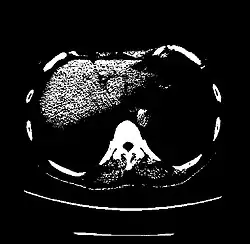

The Hounsfield scale (/ˈhaʊnzfiːld/ HOWNZ-feeld), named after Sir Godfrey Hounsfield, is a quantitative scale for describing radiodensity. It is frequently used in CT scans, where its value is also termed CT number.

A practical application of this is in evaluation of tumors, where, for example, an adrenal tumor with a radiodensity of less than 10 HU is rather fatty in composition and almost certainly a benign adrenal adenoma.[31]